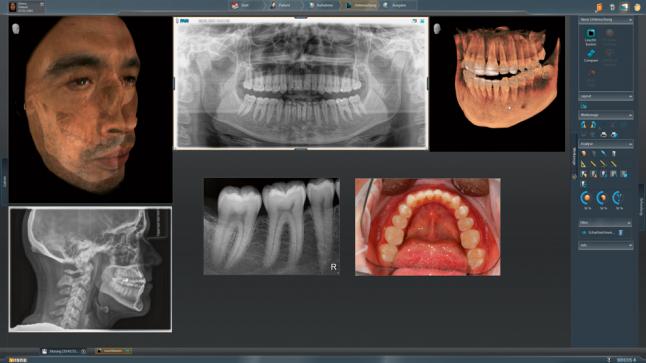

ORTHOPHOS SL 3D – это полный спектр обследований рентгенологии для стоматологической клиники любого уровня. Помимо получения снимков HD качества, важным моментом являются дополнительные пути для развития, которые появляются вместе с интеграцией в рабочий процесс Sirona.

Интегрированная имплантология с GALILEOS Implant

Все манипуляции, связанные с операциями имплантологического плана эффективны и безопасны. Для того чтобы наиболее оптимальным способом спланировать лечение, есть возможность совмещения цифровых слепков и рентгеновских изображений и объединения данных SIDEXIS 4 и CEREC 44.

Модернизированный сенсорный экран Easypad с понятным и удобным интерфейсом позволяет выставить наилучшие параметры контрастности и разрешения. Систематизация данных по диагностике становится значительно удобнее и проще с ПО обработки изображений SIDEXIS 4, ORTHOPHOS.

1. Двух-и трёхмерные снимки совмещаются в одной программе

2. В одном окне можно сравнивать разные 3D-результаты

3. Считанные минуты уходят на просмотр анамнеза пациента.

Временная шкала Timeline – это мгновенное получение информации полного спектра проведённых обследований пациента в порядке хронологии. В результате – экономия рабочего времени и повышение качества работы в целом.

Благодаря интегрированию в рабочий процесс Sirona специалисты клиники имеют возможность составлять различные схемы лечения, в том числе включая комплексную имплантологию с использованием ПО GALILEOS Implant и хирургических шаблонов (например, шаблонов CEREC 2), а также диагностику и терапию дыхательных путей с помощью SICAT AIR и SICAT OPTISLEEP.